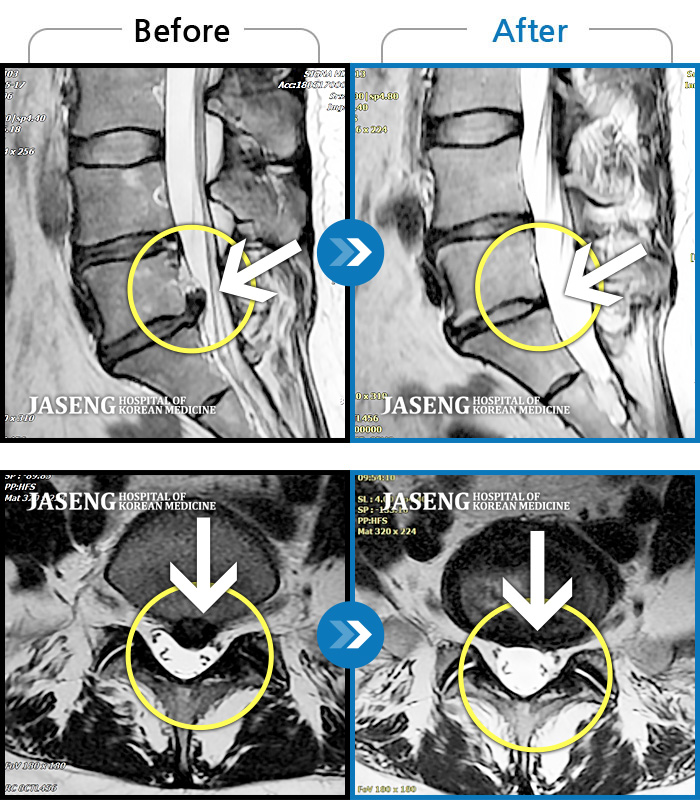

허리디스크

부천 · 최요섭

허리굽히는 동작을 한 후 우측 골반통증 및 우측 하지외측 저림, 근력저하가 있었다.

촬영시기

2023.06.15 ~ 2024.03.29

2024.04.05